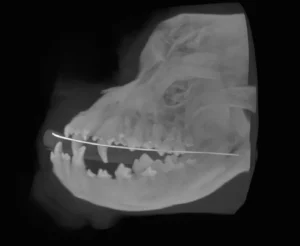

With this CT imaging system the entire head can be imaged in a single 18 second scan, allowing evaluation of teeth, jaw bones, maxillofacial anatomy, sinus and nasal cavities. CT images are composed of slices which allows millimeter by millimeter detailed assessment. In addition, a computer-generated three dimensional image may be produced. These images are superior to regular x-rays for evaluation of maxillofacial fractures, temporomandibular joint dislocations, and oral cancer.

Sample Images